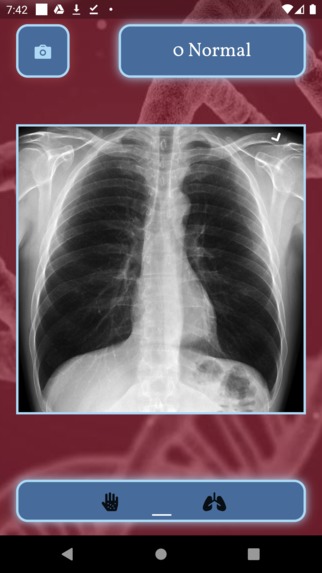

Artificial Insight accurately detects cases of melanoma, a form of skin cancer, through pictures of colored pigments in skin that often resemble moles. Our app also accurately distinguishes between chest x-rays that are either healthy, have pneumonia, or have the coronavirus. The user can choose to either select a photograph of their skin or an image of a chest x-ray. On the left, they can upload a picture of a mole on their skin and the app will tell them whether they have signs of melanoma. On the right, the user can upload an image of a chest x-ray, and the app will tell them whether the x-ray provides indication of pneumonia or COVID-19. The app has an extremely rapid diagnosis response for optimal user experience.

Because of this, we decided to create an application that provides easy methods to determine whether one has skin cancer, pneumonia, and/or COVID-19. It is extremely easy for an average citizen to simply take a picture of a mole on their body and use the app to determine whether or not they have signs of skin cancer. Similarly, x-ray machines are readily available in community physician offices, urgent care clinics, and hospital emergency departments, and they can provide images for diagnosis rapidly. According to the UCLA Department of Radiology, chest imaging plays a very important role in the early diagnosis and the treatment planning for patients with suspected or confirmed COVID-19 or pneumonia chest infections. Thus, we hope that our mobile application will allow citizens to be able to diagnose certain diseases early so that they will be able to obtain the treatment they need more rapidly.